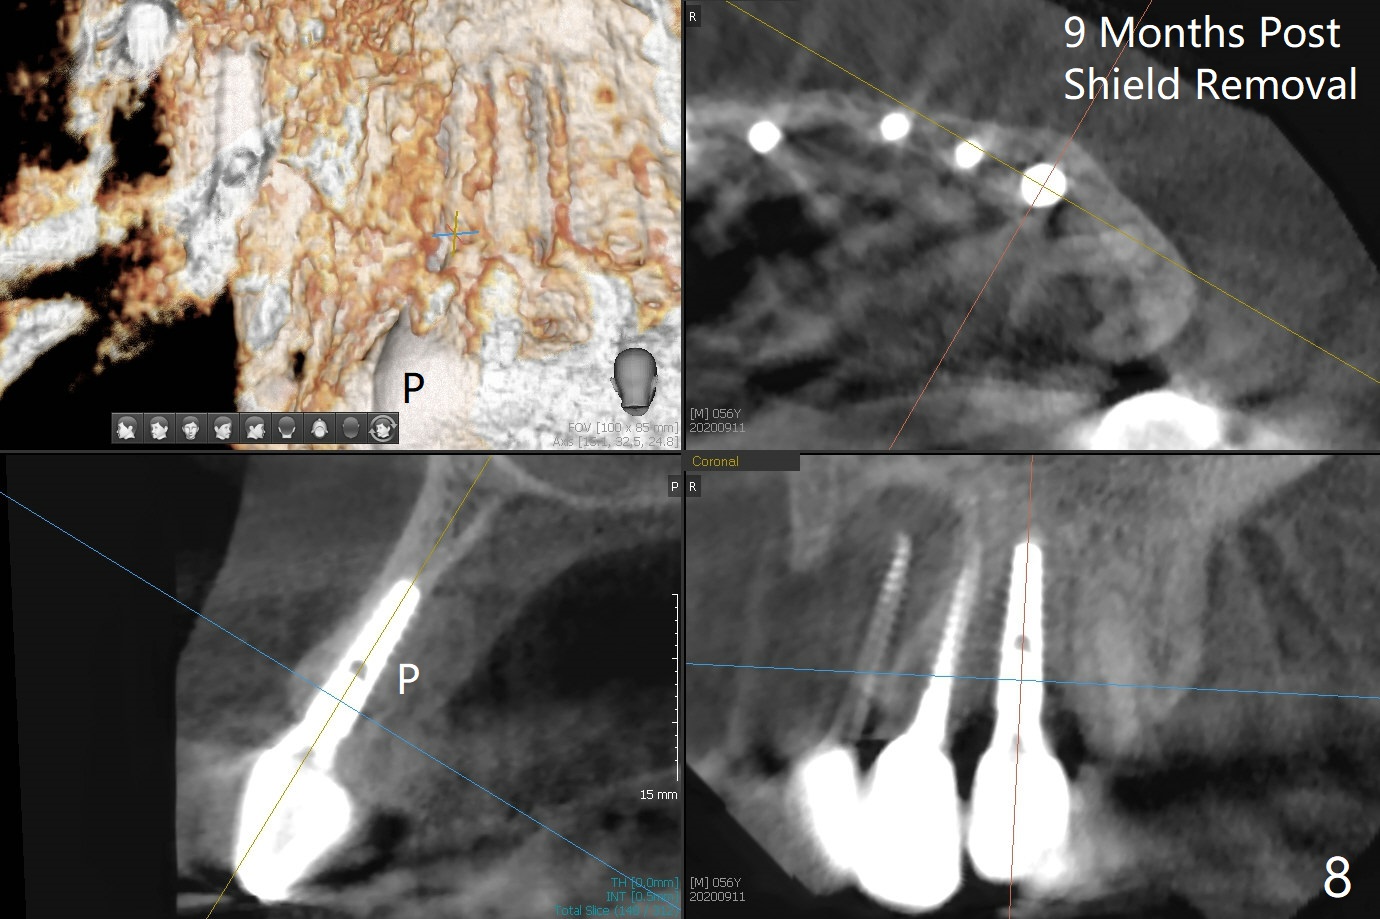

There is no obvious black triangle between the implants at #8-11 (Fig.1 post infiltration). Following papilla (Fig.2 *) sparing incision and elevation of the buccal flap, the fenetration of the buccal plate around the socket shield (Fig.3 S) is found at #11; there is a distal defect with granulation tissue (*). After shield and granulation tissue removal, the coronal implant is found exposed (Fig.4 until osteotomy). The relatively flat surface of IBS implant is apparently less likely to develop periimplantitis. With periosteal relief and placement of sticky bone (Fig.7 *), PRF and 6-month membrane, the wound is closed with 4-0 PTFE suture (Fig.5). Failure of socket shield is related to retention of the apex (Fig.6 <). Probe before extraction and remove apex and gutta percha. There appears no buccal or palatal (P) defect 9 months post shield removal (17 months post cementation, Fig.8), although the bone density palatally is low. Although the sagittal section (Fig.9 (lower left panel) shows the absent palatal plate at #10, the 3-D image and the coronal section do not (upper let and right panels). The 2.5 mm implant at #9 appears to have been placed buccal (Fig.10 B), although the buccal crest is present. In contrast the 2.5 mm implant at #8 appears within the bone boundary (Fig.11). The soft tissue remains healthy at #8-11. Bone graft will be done if needed.